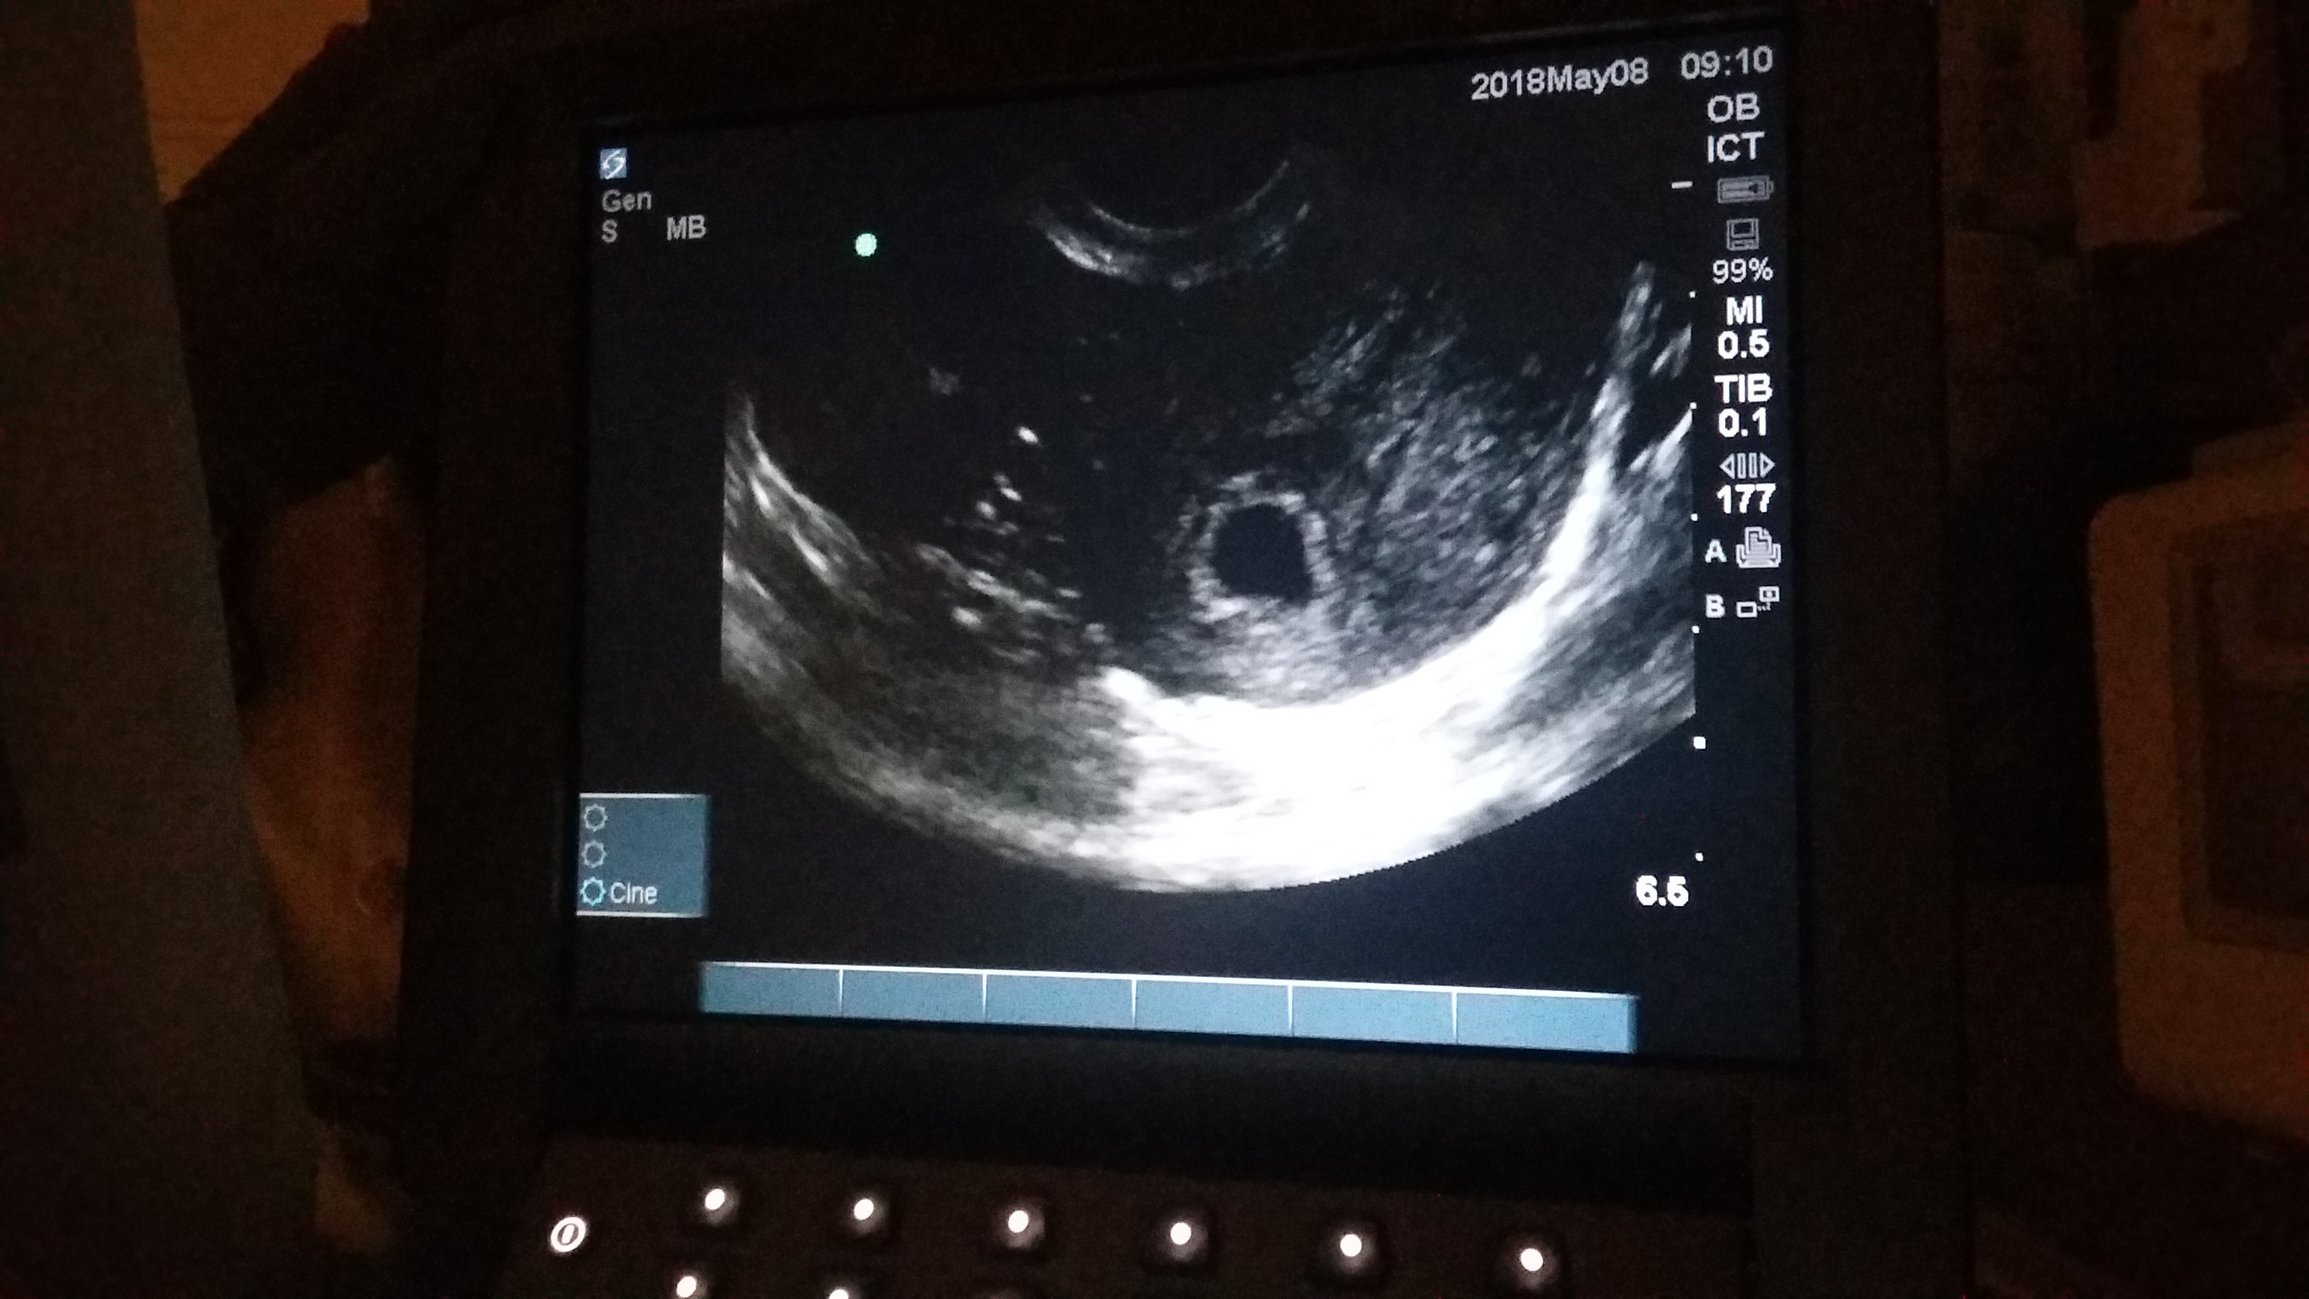

• The baby is where it's supposed to be. I'm so relieved! It's still too early to see it but you can see the sac. And I found out I am 3 days further along than I thought going by measurements